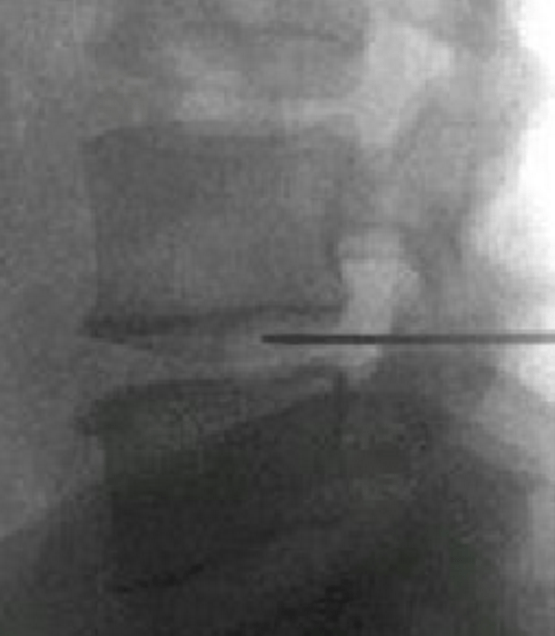

颈、腰椎间盘射频微创手术

经过多年的发展,现在的延安大学咸阳医院疼痛科在诊疗技术上已经达到一流的水平。尤其在颈、腰椎间盘突出微创治疗方面,手术量居地区前列,脊柱压缩骨折椎体成型术、颈、腰交感神经射频调控微创手术、三叉神经痛、带状疱疹后神经痛以及外周血管介入、肿瘤微创介入、内脏出血等介入治疗方面,为地区最优秀的疼痛科之一。